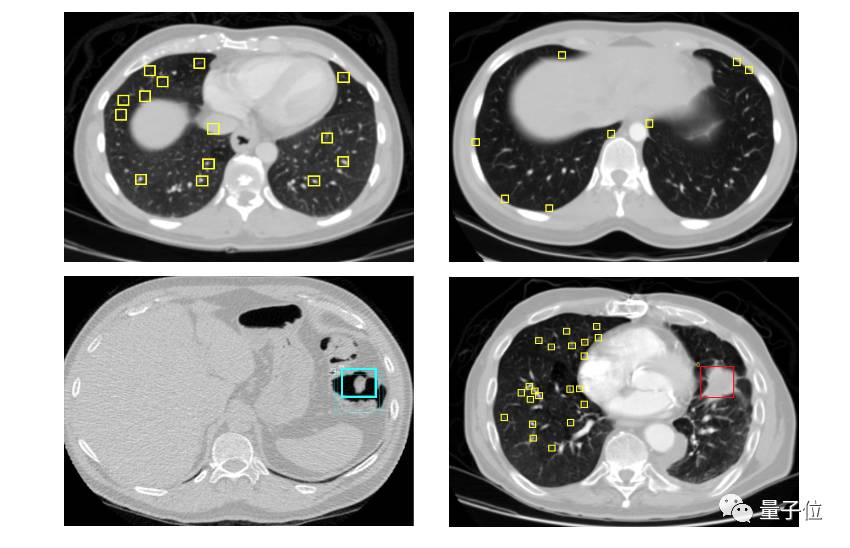

图3:带有奇怪组织的CT图像样本。

看着论坛的帖子,我发现所有的团队都在做类似的工作,我也在寻找一个能直接上手的方法。在观察CT扫描图像时,我发现了一些其他的事情。与LUNA16数据集一样,大部分的工作集中在识别肺结节上。然而,当癌症发展时,它们转变成肺肿块或更复杂的组织。并且我注意到,当扫描图像中有很多“奇怪组织”时,它发展为癌症的概率更大。此外,在很多CT图像中,我的结节探测器没有发现任何结节,这造成了一些很不好的假阴性现象。

在训练集中有10例存在上述现象,其中的5例为癌症病例。为了解决这些严重的假阴性,在扫描时,需要检测获得奇怪组织的数量。很幸运,在LUNA16数据集上包含了很多这样的样本,所以我很快对数据集进行标记并训练了一个U-net网络。加入奇怪组织检测器后,效果不错,我因此提高了本地CV值和LB上的排名。因为它对于不同的模型提升不同,很难评定实际效果,但我认为它大约提升了0.002-0.005。说实话,我认为这种改进是一个创新性的补充。以下是一些包含有奇怪组织的样本。